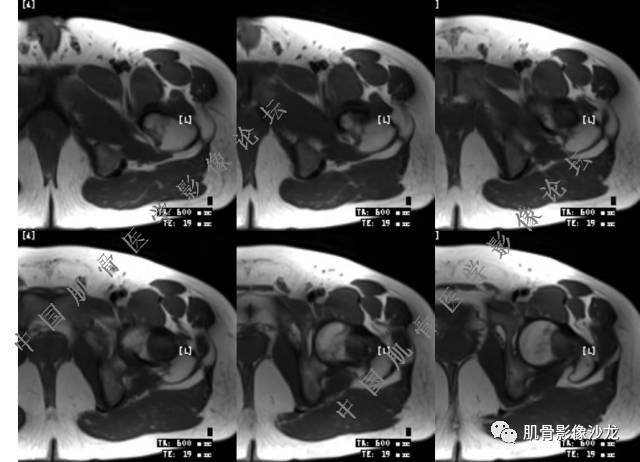

葛英霖 20:10 判断恶性程度需要看骨髓内浸润的是肿瘤还是水肿 ,从目前看,骨肉瘤是要考虑的

张小林 20:13 磁共振有双低信号,结合CT确实要考虑有纤维成份。

夏威夷的风 20:15 T1WI

葛英霖 20:19 @关舒元-河南省人民医院影像科 有可能,也不确定,增强不如t1

张小林 20:23 富含巨细胞骨肉瘤?

Echo 20:23 我个人觉得,17岁男性,病灶发生在原干骺端区域,溶骨性骨质破坏,似有肿瘤骨,有软组织肿块形成,从常见病发生率来说,骨肉瘤还是要考虑的

葛英霖 20:24 这个部位有一个需要鉴别的就是软骨母

葛英霖 20:26 可以发生在干骺端